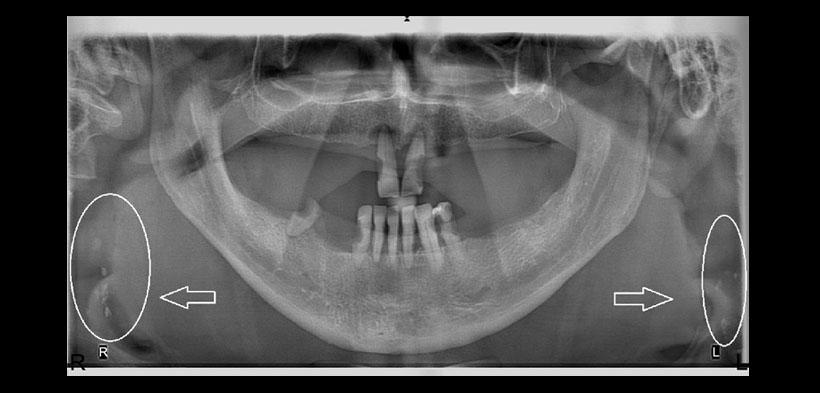

Fig. 1. Radiografía panorámica de un paciente de 76 años de edad. Se evidencia múltiples radiopacidades bilaterales compatibles con probables ateromas dentro de la arteria carótida (círculos blancos).